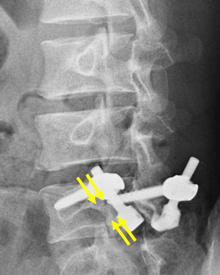

分離部修復術

腰椎分離症に対する手術は主に2つで、分離部修復術と椎体間固定術があります。椎間板の傷みがないもしくはあってもごく軽度か、20歳代までには適応となります。せなかを切開し、瘢痕組織や滑膜組織などの存在する分離部をきれいにして、自家骨(腸骨など)や人工骨などを移植します。移植した骨がしっかりつくように、スクリューやフックなどを用いて、分離部を圧着します。原則、手術翌日より硬性のコルセットを装着し、起立・歩行を開始します。十分に骨癒合が得られれば、後にインプラントを抜去しますが、必ずしも抜去しないこともあります。

第5腰椎分離症の術前レントゲン。矢印が分離部で骨が離れています。 -

第5腰椎分離症の術後レントゲン。分離部に骨が移植され骨癒合が得られています。